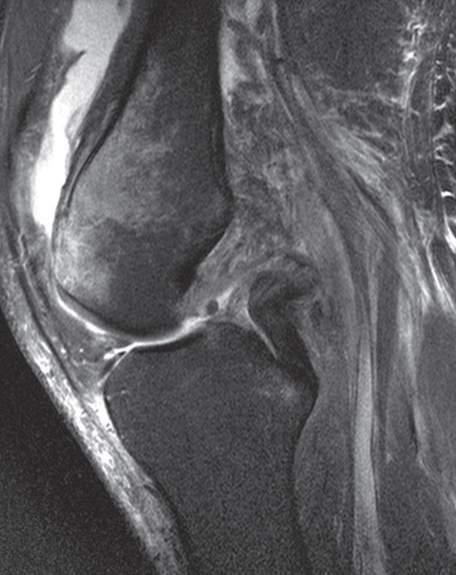

Fig.1.4 Sagittalviewoftheknee.(FromKangHS,AhnJM,ResnickD. MRIofthe Extremities.Philadelphia:Saunders;2002:341.)

Plainradiographyisindicatedinall patientswhopresentwithkneepain (Fig.1.6).Basedonthepatient’sclinicalpresentation,additionaltestingmay bewarranted,includingacompletebloodcount,erythrocytesedimentation rate,andantinuclearantibodytesting.Magneticresonance(MRI)andultrasoundimagingofthekneeisindicated ifinternalderangement,aseptic necrosis,oranoccultmassortumoriss uspected,orifthediagnosisisin question( Figs.1.7 and 1.8).

Fig.1.7 SagittalfatsuppressedT2-weighted(FST2W)magneticresonance(MR)imageofanacute posteriorcruciateligament(PCL)tear.Theproximalligamentiscompletelydisruptedfromitsfemoral attachment,andthetornendofthePCLisvisualized (whitearrow).Notealsotheprominenttrabecular bonebruisinginthedistalfemurandtheprominentjointeffusion.(FromWaldmanSD,CampbellRSD. ImagingofPain.Philadelphia:Saunders;2011:Fig.148.3.)